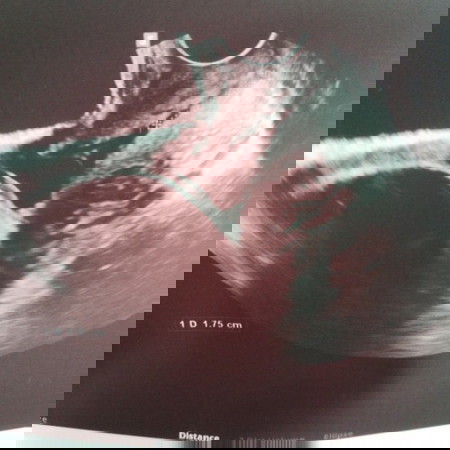

6 months and 2 week na ako, may y shaped cervix ako base po sa ultrasound ko tlga po bang nakaka sama ito 😔saka ano po ba tlga kailangan po ba maikli or mahaba sya? #1stimemom #advicepls #firstbaby